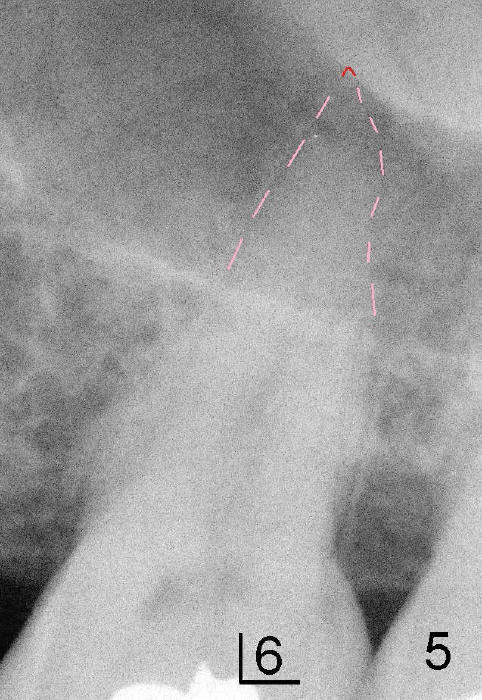

Prior to placement of 6x17 mm soft tissue level implant (Fig.1), the same size of tap is used. When the latter is removed, there is a small defect in the buccal wall of the osteotomy (mainly in the palatal socket) with the intact sinus membrane. There is no intraop or postop nasal hemorrhage. The patient returns for restoration 7 months postop; it appears that there is osteo-integration (Fig.2 with the mesial gap getting smaller (>)). The gingiva is healthy buccal (Fig.3: B) and palatal (Fig.4: P). The mesial gap is closed with formation of dense bone 4 years post cementation (Fig.7). Fig.5 is the preop PA of the patient, which shows that the palatal root (pink dashed line) is above the sinus floor and surrounded by the lamina dura. Fig.6 is a coronal section of the 2nd molar of another patient, which shows that the palatal root is 5-6 mm above the sinus floor. Upper Molar Immediate Implant Follow-Up Xin Wei, DDS, PhD, MS 1st edition 10/13/2013, last revision 05/18/2018